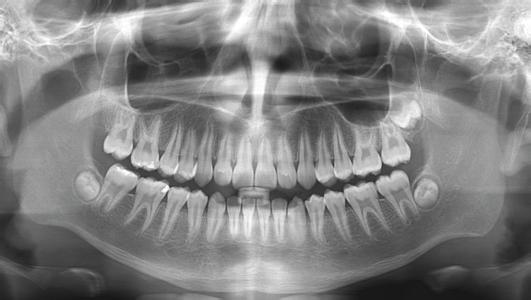

Une radiographie panoramique vous sera demandée pour avoir une vision d’ensemble de la bouche et des voies aériennes supérieures.